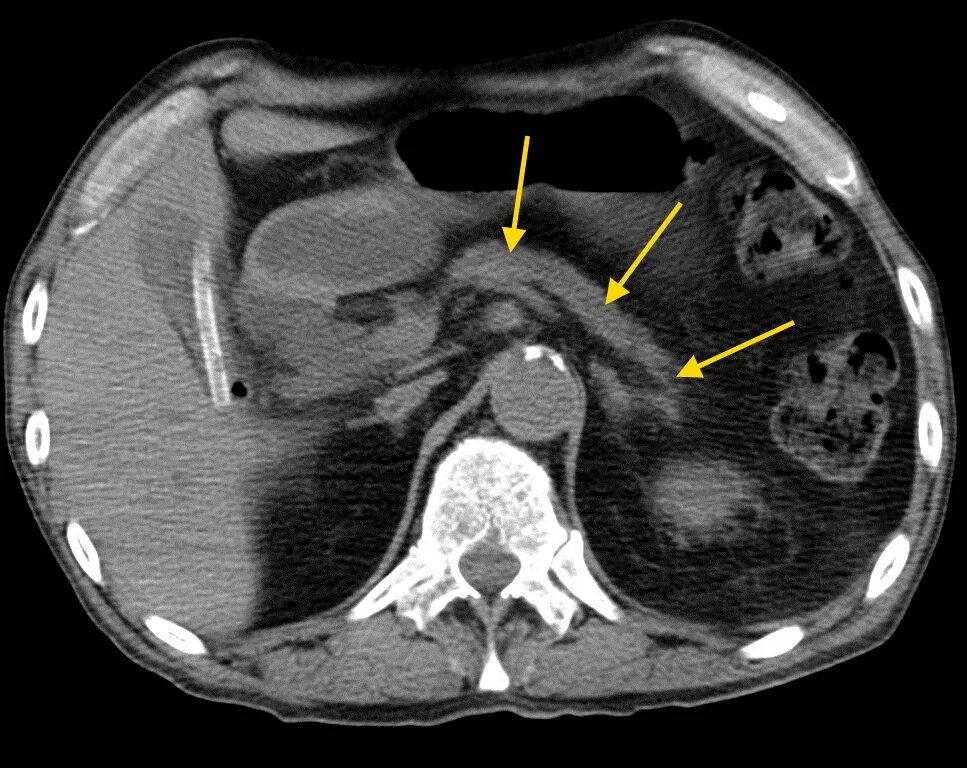

Мрт кисты поджелудочной